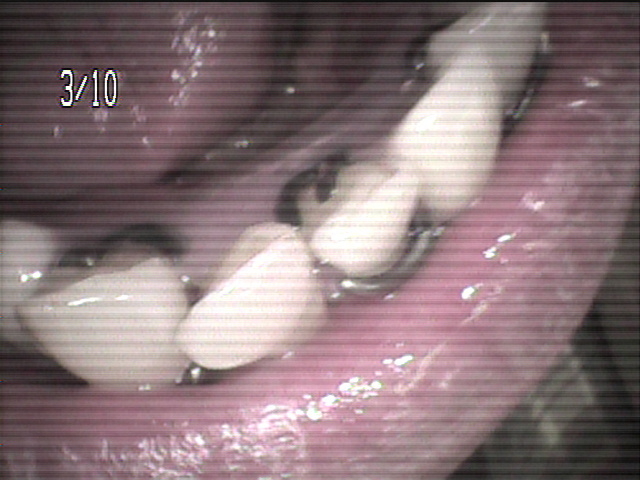

本日、出来上がりました自費の部分入れ歯ー下顎メタルプレートの症例です。

81歳の女性OUさんはとけも若々しいかたで、上下ともに、ぶぶん入れ歯ですが、今回は下顎の左右の奥歯のメタルプレートの入れ歯を新しく作りました。

自費によるメタルプレート義歯で、薄く丈夫な義歯として、とても舌感の良好な状態にすることができ、さらに自由な義歯の設計ができるため、残っているはにかける針金は白金加金で作成し、残存歯にやさしい設計となっており、舌に触れるバー部分はコバルトクロム合金で、丈夫に薄く作ってあります。